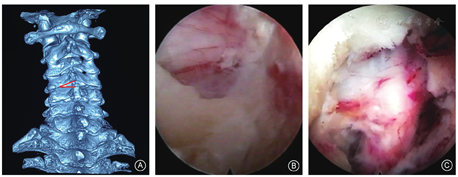

预防措施包括术中首先要用两指法推移内脏鞘和血管鞘,扪及椎体和椎间盘表面,食指和中指分别向内、外侧推开以保护食管和颈部血管,术中透视观察气管阴影可帮助确定气管、食管复合体偏离中线的位置;在两手指之间穿刺,最好接近椎间盘表面的中部进针,避免损伤颈长肌及其表面交感链,穿刺角度不宜太大(一般≤15°),以免损伤对侧椎动脉等组织;避免使用环锯等锐性器械扩张,以免损伤周围血管包括小动脉和食管等,术中X线透视监视穿刺和置管位置(图1)。

后路经皮内镜穿刺置管时有进入椎板间隙损伤脊髓的风险,需要X线透视定位穿刺点及方向,穿刺、扩张和置管均要抵达椎板和关节突骨质,避免进入椎板间隙。开窗和减压过程中也有损伤神经的风险,在内镜下清晰显露"V"点后应用金刚砂磨钻磨除骨质,要牢固控制磨钻方向和深度,平移摆动磨钻磨除骨质,避免下压磨头,以免损伤神经,椎板磨薄后可用内镜下枪钳咬除。开窗后切除黄韧带外缘的韧带,显露硬膜囊外缘,沿硬膜囊外缘延续部显露神经根,探查、摘除脊髓外侧突出的髓核(图2)。Yang等[8]报告42例后路经皮内镜手术病例,其中1例术后发生对侧下肢神经功能障碍,考虑与术中牵动脊髓有关,经保守治疗3个月好转;1例椎间盘突出巨大,并被脊髓包绕难以分离,改行前路颈椎间盘切除融合术(anterior cervical discectomy fusion, ACDF)。因此,应选择合适的适应证,避免过度牵拉脊髓和神经。